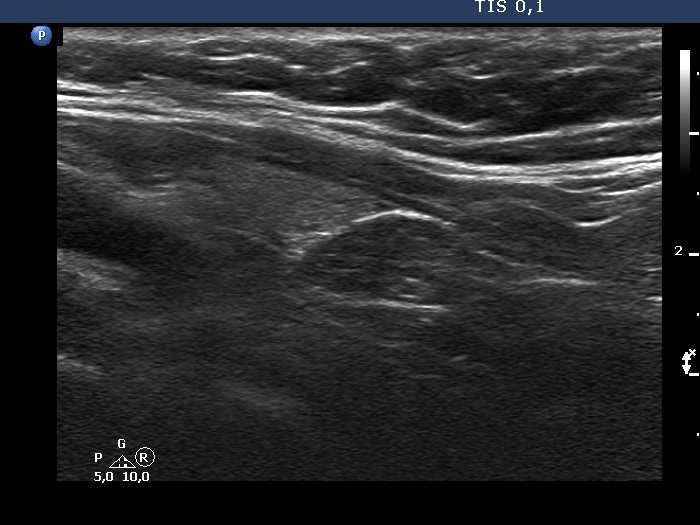

Ultrasonography. The thyroid was echonormal. According to the PET-positive lesion, there was a moderately hypoechoic nodule in the middle-dorsal part of the left lobe. The lesion presented with perinodular blood flow. In the transverse section, it appeared that there was another nodule in the lower pole of the lobe. At the same time, based on the longitudinal section, it was not an oval, nodule-like lesion. The mass proved to be longitudinally elongated in the caudal direction and was avascular.

An anatomical structure running perpendicular to the transducer looks round or oval, and it can look deceptively like a discrete lesion. If this occurs in the thyroid region, it can be mistaken for a nodule. The most common examples of this are the carotid artery, the jugular vein, and the esophagus, the latter usually appears on the dorsal surface of the left lobe of the thyroid gland. The key is always to examine the patient in two perpendicular planes. An examination parallel to the anatomical structure (in this case in the longitudinal section) shows that it is a tube-like, longitudinal structure. In this case, it was very likely a dorsal muscle.

A muscle used to be avascular on Doppler mode.